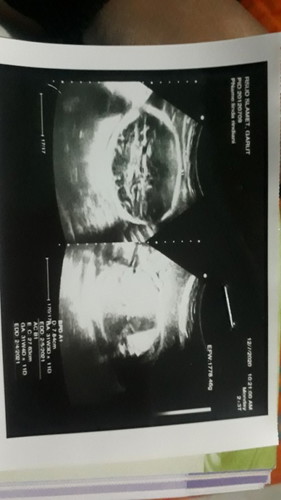

Bunda, di kehamilan trimester kedua biasanya mual muntah ataupun pening mulai berkurang. Namun, ketika satu masalah hilang biasanya masalah lain datang bukan ? Pengalaman saya di trimester kedua mual muntah mulai berkurang menjadikan nafsu makan sedikit-sedikit kembali normal. Tapi ingat yaa Bun, pola makan harus tetap di jaga dan asupan nutrisi harus seimbang. Bagi bunda yang ngidam pedas, makan pedas sewajarnya jangan berlebihan untuk menghindari perut mulas berlebih dan kambuhnya penyakit lambung. Mulai jadwalkan pertemuan dengan dokter untuk USG. Eitsss bukan untuk melihat Jenis Kelamin bayi saja ya bun, tapi juga untuk melihat kondisinya. Tahukah bunda? Ketika melihat Bayi kita di monitor saat USG bisa membuat hati sangaaat bahagia dan senyuman refleks terukir dibibir. โค๐ #DearParentsTAP tetap semangat menjalani kehamilan, ibu sehat insyaa Allah bayi sehat. Think positive โค